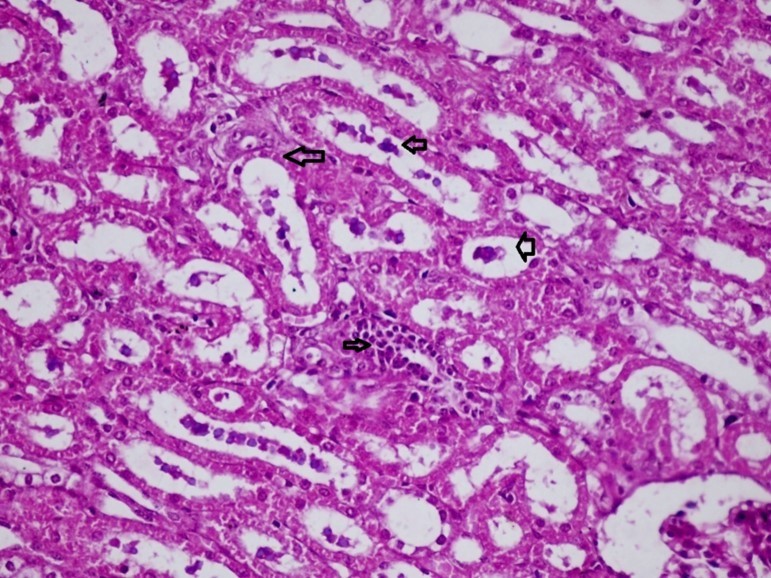

Figures 6.kidneys (dead cattle less than 1 year old) showed severe hydropic degeneration of renal tubular epithelium accompanied by dilated renal tubules, vesicles formations and casts (arrows). (H&E, X 100)

Figures 7.kidneys (dead cattle less than 1 year old) showed severe hydropic degeneration of renal tubular epithelium accompanied by dilated renal tubules, vesicles formations and casts (arrows). (H&E, X 60)

It is an ELISA that detects antibodies against the highly conserved non-structural (NS) protein of the FMD virus. The test can therefore be used for all species. The positive reactions mean the presence of infectious agent of FMDV. The indicate anaemia. Al-Rukibat et al., (2015) recorded significant increase in PCV in FMD infected sheep. Also, Elitok et al., (2005) found that PCV was higher in FMD infected animals than in healthy free ones. However, from our histopathology of kidneys of infected animals it was observed that it suffers degenerations and focal necrosis in both cortex and medulla, and as erythropoietin is a vital substance produced by the kidneys and is responsible for synthesis of RBCs (erythropoiesis), one could explain main reason for anemia in FMD infected animals (Jubb et al., 1991).